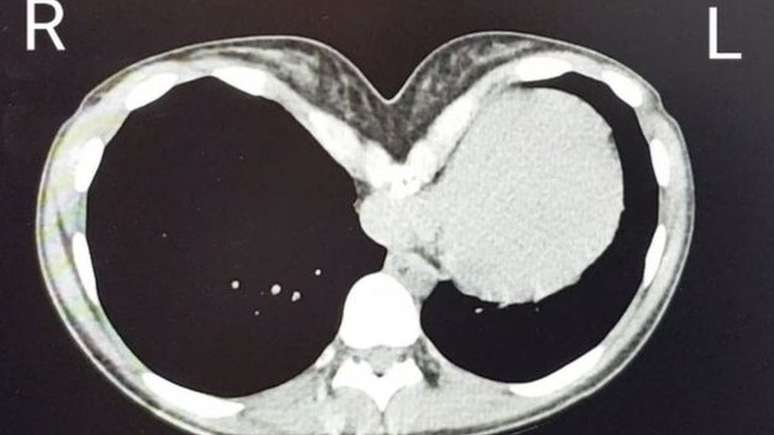

Katie diz que seu coração foi esmagado por seus ossos

Foto: Katie Bruce / BBC News Brasil